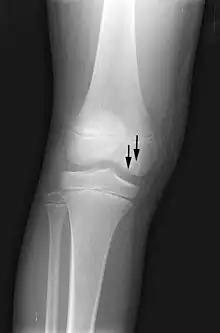

X-ray images of avascular necrosis in the early stages usually appear normal. In later stages it appears relatively more radio-opaque due to the nearby living bone becoming resorbed secondary to reactive hyperemia.[2] The necrotic bone itself does not show increased radiographic opacity, as dead bone cannot undergo bone resorption which is carried out by living osteoclasts.[2]

Radiography of total avascular necrosis of right humeral head. Woman of 81 years with diabetes of long evolution.